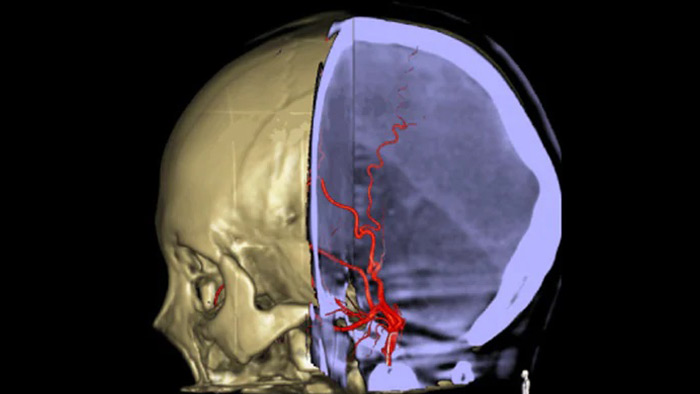

SmartCT Vaso IV

Comprobar la ubicación y la longitud del coágulo

SmartCT Vaso permite la visualización más allá del coágulo con imágenes periprocedimiento de las caras distales de los vasos en el accidente cerebrovascular isquémico. SmartCT Vaso es una técnica de adquisición basada en una TC de haz cónico y una inyección de contraste intrarterial. Permite la visualización más allá del coágulo con imágenes periprocedimiento de las caras distales de los vasos en el accidente cerebrovascular isquémico. Mediante el llenado retrógrado, se ven las estructuras de los vasos antes y después del coágulo. SmartCT Vaso 3D Roadmap puede utilizarse para visualizar los dispositivos de recuperación de coágulos.

Las referencias anatómicas apoyan una navegación 3D precisa

SmartCT image

SmartCT Roadmap proporciona referencias anatómicas para apoyar la navegación precisa de la aguja guía, el catéter y el dispositivo al coágulo.